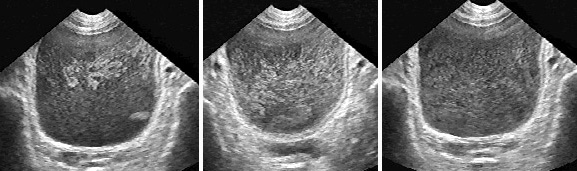

Рис. 3. Сонограммы мочевого пузыря в норме и при аномалиях развития почек и мочеточников. Выбросы из мочеточников помогают установить положение и число устий, подтвердить тем самым наличие одной, двух или трех функционирующих почек (Поперечное сканирование, секторный датчик 5 МГц, “Siemens SL-1”).